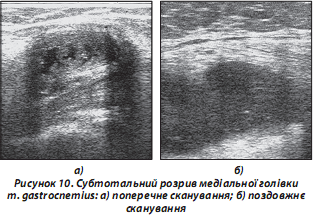

в) повний розрив (УЗД-ознака — гематома в місці м’язово-сухожильного переходу). М’яз при поперечному УЗ-скануванні «відірваний» від місця прикріплення (рис. 10). Давність гематоми визначається за такими ознаками: реєстрація перифокального кровотоку за даними допплерівського УЗД, а також наявність гіперехогенних включень (нитки фібрину) свідчить про підгострий/хронічний процес;